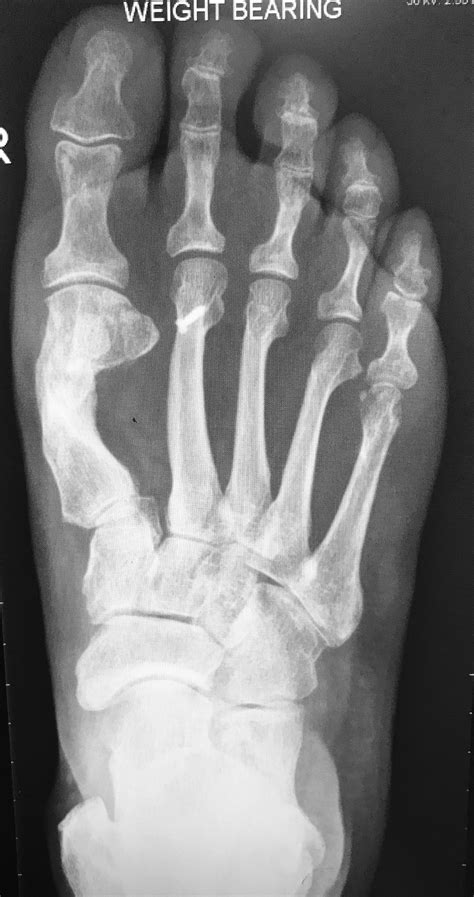

Can You See Torn Ligaments On X Ray Before Surgery